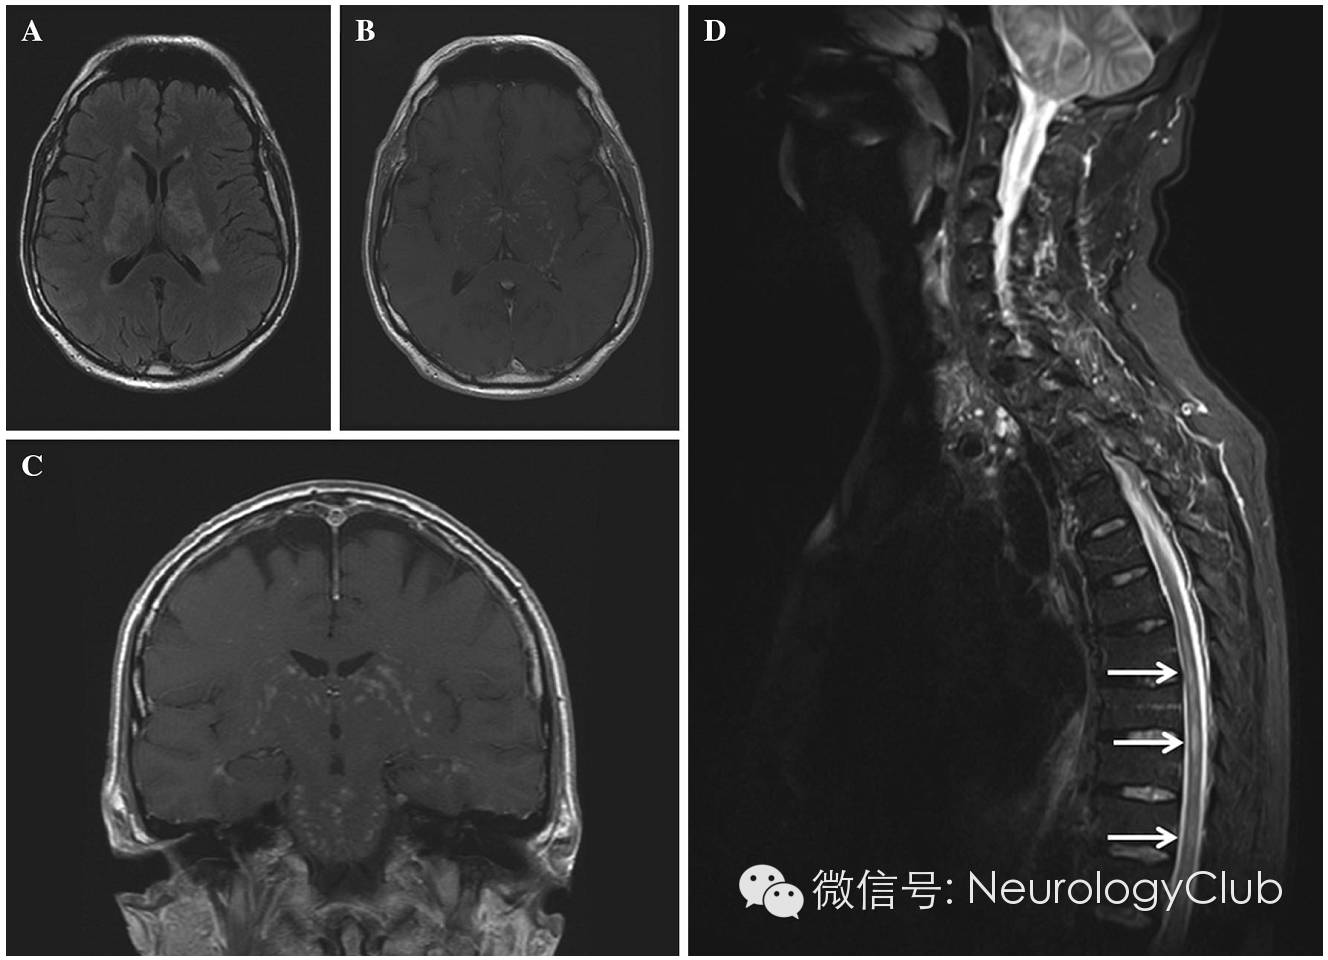

59岁男性,开始表现为面神经麻痹和三叉神经支配区感觉迟钝,后数月内出现意识模糊,下肢痉挛和小脑综合征,体重下降20kg。头颅和脊髓MRI可见分布于CNS的双侧非对称性T2高信号,伴线状,结节样和血管周围强化(图1)。灰白质均受累,特别是脑干,小脑和内囊。神经结节病,淋巴瘤以及CLIPPERS(类固醇激素反应性慢性淋巴细胞炎伴脑桥血管周围强化征)均需考虑。腰穿提示炎症性改变(细胞数14,蛋白0.94g/L),未见恶性肿瘤细胞,细胞培养阴性。未行脑脊液病毒PCR和抗体检测。患者拒绝脑活检。

(A:黑水像,可见双侧不对称的脑室旁高信号;B-C:T1增强,脑干和大脑半球灰白质不均匀的线状和血管周围强化;D:T2WI,多发胸髓内高信号)

神经系统症状通常出现在复发期或确诊后12-25月,但也有例外。本例患者MRI上病灶分布和表现不典型(图1)。脊髓浸润在非霍奇金淋巴瘤特别是套细胞淋巴瘤中罕见。非霍奇金淋巴瘤脑内受累与原发性CNS淋巴瘤的病灶相似(均匀强化)。患者的MRI表现为不均匀的结节状,线状和血管周围强化,激素治疗后好转,提示首先考虑结节病,淋巴瘤或CLIPPERS综合征。